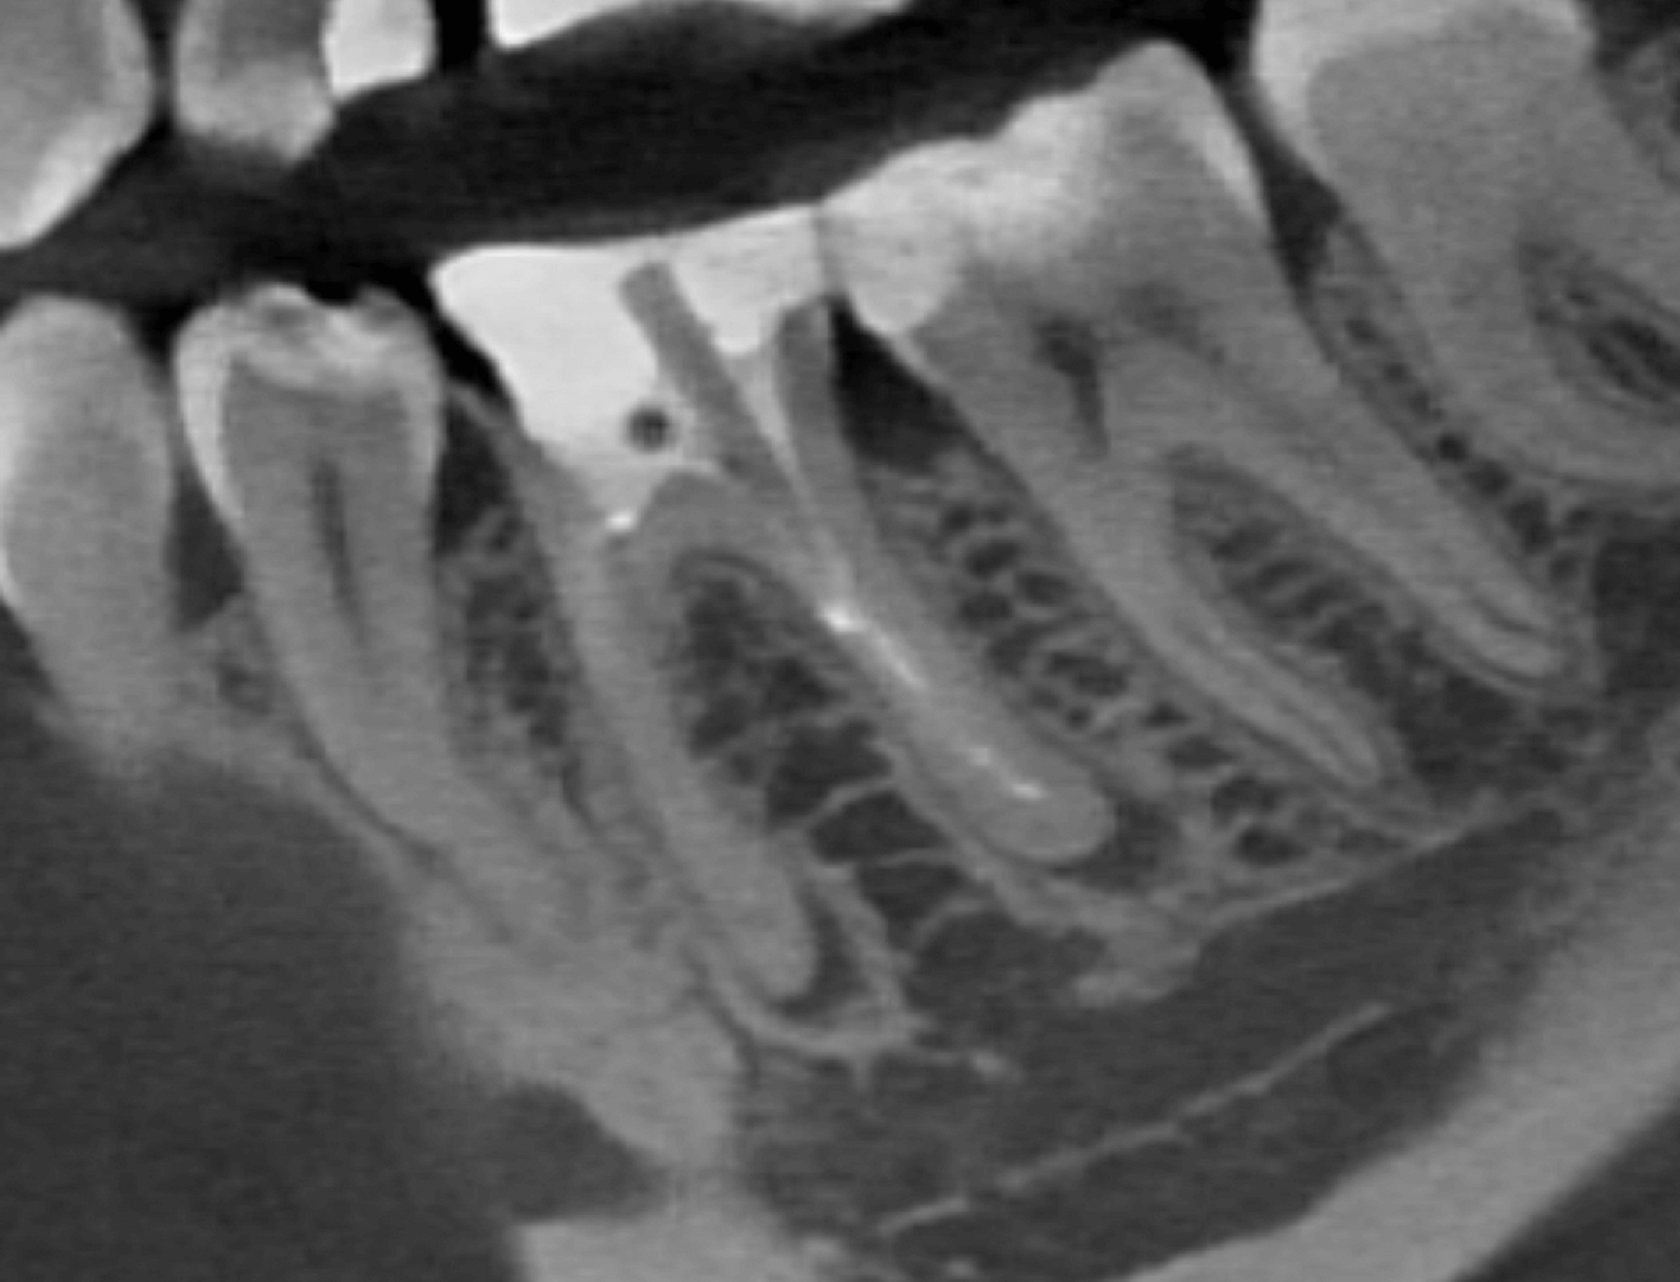

2. В первое посещение выполнена эндодонтическая ревизия, удалены сломанные инструменты, корневые каналы обработаны и временно обтурированы препаратом на основе гидроксида кальция сроком на 2 недели. (Фото 4)

3. Пациентка нарушила график приемов, повторное обращение в клинику через 10 месяцев после начала лечения: временная пломба сохранена, временный обтурационный материал сохранен в корневых каналах, по КЛКТ отмечается значимое уменьшение очага перирадикулярной деструкции. (Фото 5,6,7)